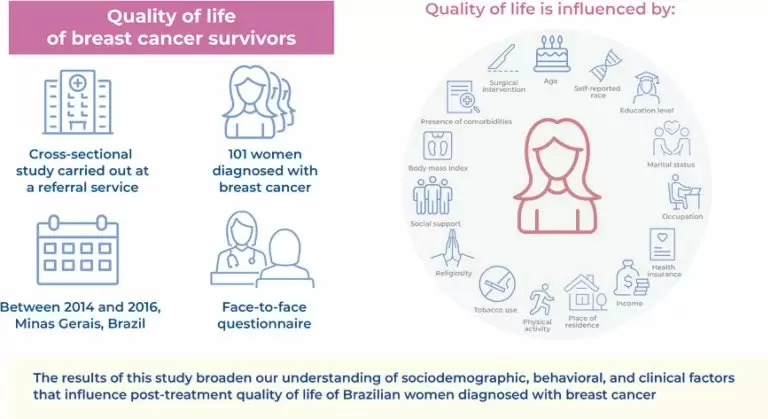

14/Mar/2024

Quality of life of women who underwent breast cancer treatment relative to sociodemographic, behavioral, and clinical factors

Quality of life of women who underwent breast cancer treatment relative to sociodemographic, behavioral, and clinical factors

DOI: 10.31744/einstein_journal/2024AO0585

Highlights Sociodemographic, clinical, and lifestyle factors impact the quality of life of breast cancer survivors. Breast cancer therapy may affect future perspectives and emotional, cognitive, and sexual function. Some aspects of quality of life still require attention from health professionals. ABSTRACT Objective: Patients with cancer often undergo multiple extended treatments that decrease their quality of life. However, the quality of life of women with breast cancer after they undergo treatment remains underexplored in Brazil. Therefore, this study determined sociodemographic, behavioral, […]

Keywords: Activities of Daily Living; Breast neoplasms; Life style; Quality of life; Sociodemographic factors; Surveys and questionnaires